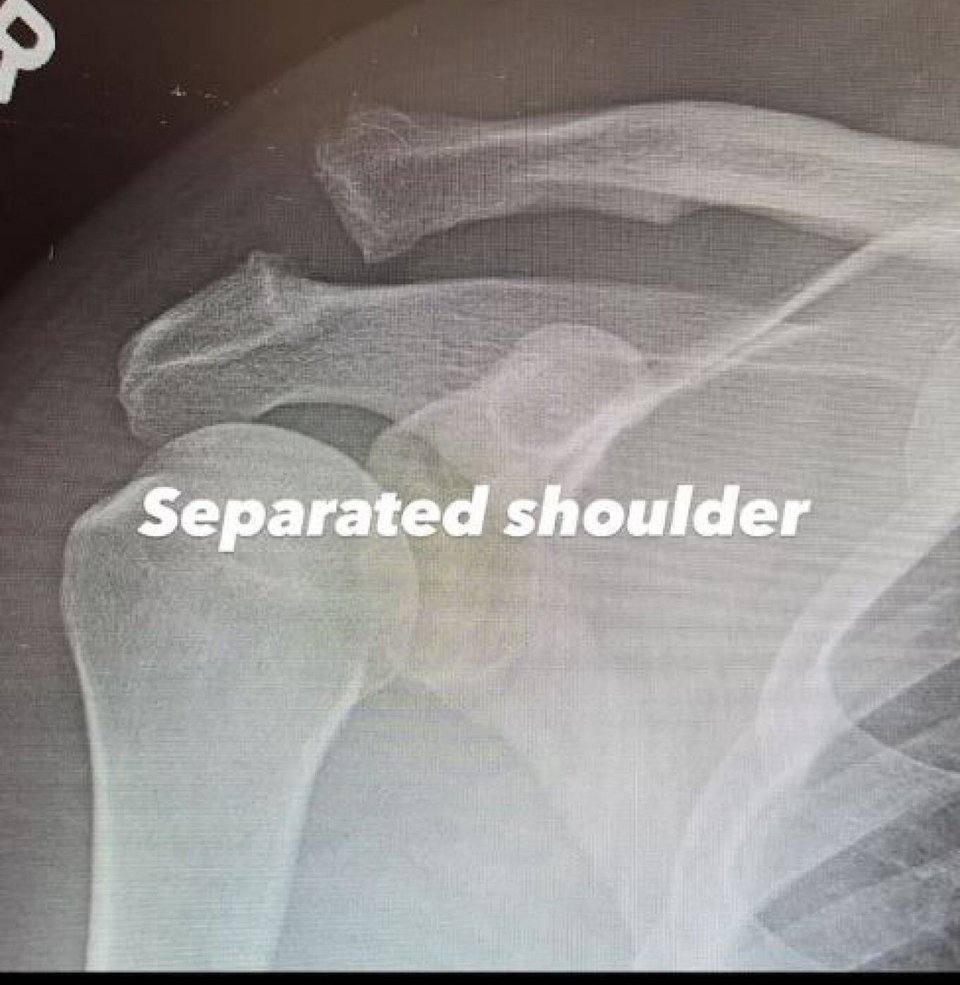

Λίγο αργότερα, με νέα δημοσίευση, ο ηθοποιός αποκάλυψε την ακριβή αιτία του τραυματισμού του. Όπως εξήγησε, είχε υποστεί εξάρθρωση ώμου, με δύο σπασμένα οστά στην περιοχή. Μάλιστα, ανάρτησε ακτινογραφίες της περιοχής, δείχνοντας τη σοβαρότητα της κατάστασης και τη βίδα που τοποθετήθηκε για να συγκρατήσει τα οστά στη θέση τους. «Εξάρθρωση ώμου», έγραψε στη λεζάντα της πρώτης ακτινογραφίας, ενώ στην επόμενη ανέφερε με χιουμοριστική διάθεση: «Βιδωμένος ώμος. Γιούπι».